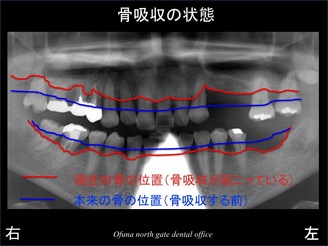

いつものように 骨吸収の状態を分かりやすくするために 骨吸収の状態を線で書いたのが以下のレントゲンになります。

青線が骨吸収を起こす前の骨の位置です。

赤線は、現在の骨の位置です。

骨が吸収してしまったのが分かるかと思います。

上顎では、歯を支えている骨の量は

前歯部で50%程度(50%の骨は吸収している)、

上顎右側の奥歯で10〜40%(90〜60%の骨が吸収している)

でした。